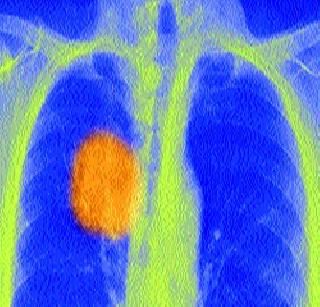

कर्करोग प्रतिबंधक पहिली लस विकसित केल्याचा दावा शास्त्रज्ञांनी केला आहे. ही लस शरीरातील इम्यून सिस्टिम सक्रिय करेल व त्यामुळे शरीराची रोगप्रतिकारक क्षमता वाढून कर्करोगाच्या गाठी नष्ट होतात

लंडन : कर्करोग प्रतिबंधक पहिली लस विकसित केल्याचा दावा शास्त्रज्ञांनी केला आहे. ही लस शरीरातील इम्यून सिस्टिम सक्रिय करेल व त्यामुळे शरीराची रोगप्रतिकारक क्षमता वाढून कर्करोगाच्या गाठी नष्ट होतात, असे त्यांचे म्हणणे आहे. ही लस यशस्वी ठरल्यास कर्करोगांसाठी ही एक महान देणगी ठरणार आहे.

या लसीचा प्रयोग कर्करोग झालेल्या एका महिलेवर करण्यात आला आहे. एखाद्या रुग्णाला लस दिली जाण्याची ही पहिलीच वेळ आहे. रुग्णाच्या शरीरात रोगप्रतिकारक क्षमता वाढवून कर्करोगाचा नायनाट करण्याचे या संशोधनामागे सूत्र आहे.

या लसीत एक खास प्रकारचे प्रोटीन एन्झाईम असून तो कर्करोगाच्या पेशी नष्ट करतो. या इंजेक्शनमुळे शरीरात अशा अॅन्टीबॉडिज बनतील की त्या शरीराची रोगप्रतिकारक क्षमता वाढवतील. या अॅन्टीबॉडिज कॅन्सरच्या पेशींवर हल्ला करतील, पण शरीरासाठी आवश्यक असणाऱ्या पेशी नष्ट करणार नाहीत. ही चाचणी यशस्वी होवो की न होवो, पण ती नक्कीच सुरक्षित असल्याचा आमचा विश्वास असून आम्हाला या चाचणीच्या निष्कर्षाची प्रतीक्षा आहे, असे एका शास्त्रज्ञाने सांगितले.